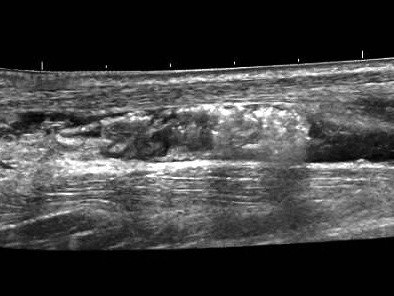

achilles tendon after high volume stripping

Another option is ultrasound guided injections for Achilles tendinopathy. In the Sonoscope clinic, we perform ultrasound guided hydrodistension injections, which inject a large volume of saline (salty water) water into the interface between the Achilles tendon and the fat pad that lies in front of the Achilles tendon. This “stripping “procedure disrupts the increased activity of blood vessels in the painful tendon, which reduces pain by disrupting this unhelpful increased blood circulation which leads to increased levels of pain. Although more recent studies have not found evidence for this mechanical effect of reducing neovascularity.

The evidence supports this procedure, although more recent studies have indicated that steroids (which are usually added with the saline) rather than the mechanical effect of stripping the tendon results in the benefits described in previous studies.